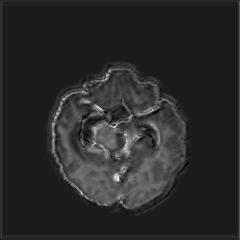

(a) (b) (c) (d)

Boundary Stream:

Fig. 2 demonstrates the output of each of the attention layers in our dedicated boundary stream. In essence, each attention layer progressively localizes the tumor and refines the boundaries. The first attention layer has learned rough estimate of the boundaries around the tumor and localized it, whereas the second and third layers have learned more fine-grained details of the edges and boundaries, refining the localization. Moreover, since our architecture leverages a dilated spatial pyramid pooling to merge the learned feature maps of the regular segmentation stream and the boundary stream, multiscale regional and boundary information have been preserved and fused properly, which has enabled our network to capture the small structural details of the tumor.